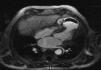

Case reportIn this report, we describe the case of an 82-year-old man, with a previous aortic valve replacement with a bioprosthesis four years previously. He was admitted for anterior STEMI with normal coronary arteries on angiography and apical ballooning. At this time the transthoracic echocardiogram (TTE) revealed a normally functioning aortic prosthesis and the apex was akinetic. He was followed at another institution where, at the first month follow-up visit, he complained of fatigue and dyspnea. TTE showed a VSD and an apical aneurysm of the left ventricle (LV) and the patient was transferred to our institution. In our department a complete TTE displayed a dilated LV, with normal global systolic function and hyperkinesia of the basal and mid segments. A large apical aneurysm was visualized with a LV to right ventricle (RV) turbulent flow suggestive of a shunt with a gradient of 90–97 mmHg (Figure 1). Contrast TTE with Sonovue® (Figure 2) and cardiac magnetic resonance imaging (Figure 3) were performed for further characterization, both showing a large LV apical aneurysm with a thrombus and a VSD with two jets of a turbulent flow to an apical RV pseudoaneurysm, also with a thrombus inside. The patient underwent corrective surgery with a Dor procedure (endoventricular circular patch plasty) combined with VSD closure and resection of the RV pseudoaneurysm (Figure 4). The procedure was successful and the postoperative course was uneventful.